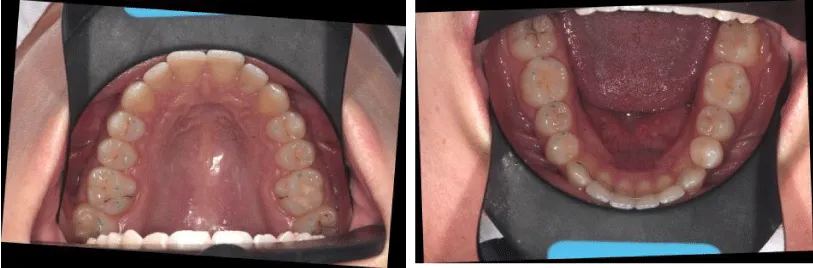

The procedure of the APTCA goes in the following sequence. After debanding patient is examined with T-scan III occlusal analysis procedure. The recording sequence is: centric occlusion, multi-bite, left lateral, and right lateral. Then occlusal foil (8 microns, Arti-Fol, Bausch, Germany) is placed between the teeth, patient is then asked to bite with the articulating paper in the mouth (Figure 2). Operator holds the articulating paper while the patient bites in his centric occlusion. These marks are then compared to the occlusal contacts viewed on the screen in patient`s centric occlusion recording (Figure 3). The highest forces on the teeth, which are seen on the screen exceeding the overall force level of 82%, have to be eliminated in the mouth. The force outliers on the screen are compared with paper marks on the patient`s teeth. The level of force does not usually correlate with the size of the occlusal mark. As described by Kerstein [20], small paper marks often tend to exhibit higher forces than larger marks.